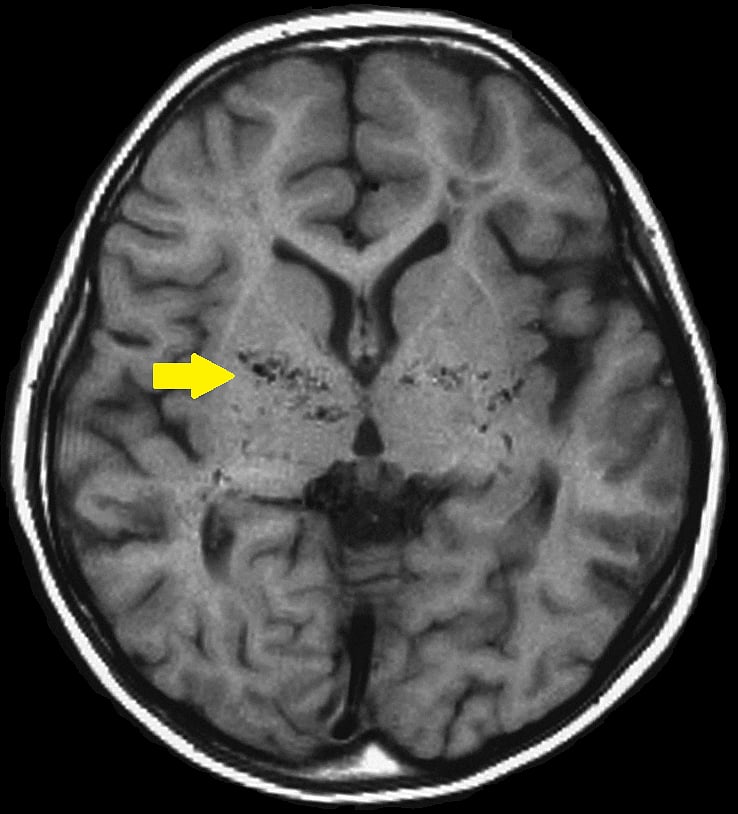

தற்போது வெற்றிகரமாக அறுவை சிகிச்சை முடிந்து சிறுமிகளும் நலமுடன் இருக்கின்றனர். இது போன்ற நிகழ்வு ஆசியாவிலே இது தான் முதல் முறை. தற்போது அவர்களது மூளையின் இடது பக்கத்தில் இரத்த ஓட்டம் மேம்படுத்தப்பட்டது ஸ்கேன்கள் மூலம் கண்டறியப்பட்டுள்ளது" என்றது.

அதனால், மூளைக்குப் போதிய அளவு இரத்தம் கிடைக்காமல், நோயாளிகள் மூளை அடைப்புக்கு உள்ளாகிறார்கள். இதனை ஈடுகட்டும் வகையில் மூளைக்கு அடியிலுள்ள நுண்ணிய ரத்தக்குழாய்கள் ஊதிப்பெரிதாகி, புதிய ரத்த ஓட்டத்திற்கான பாதையை உண்டாக்குகின்றன என்பது குறிப்பிடத்தக்கது.